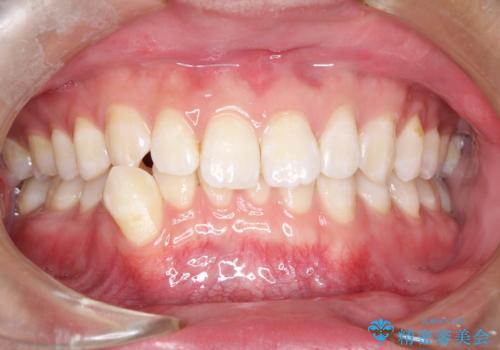

前歯がガタガタ インビザラインによる矯正

- 前歯がガタガタ、下の犬歯が飛び出ているのを主訴に来院されました。

下の奥歯を後方へ移動させてスペースを確保して、前歯を並べる計画としました。